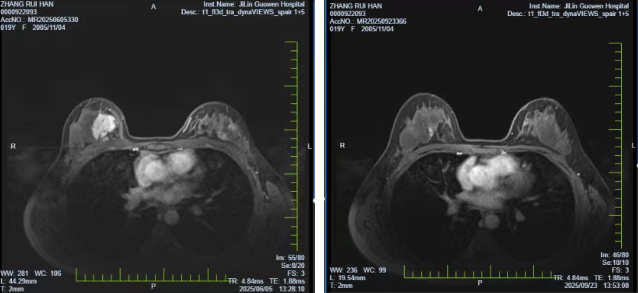

启动化疗4周期方案,联合戈舍瑞林治疗,病情达到部分缓解。为加快缩瘤进度,医院特邀天津医科大学肿瘤医院乳腺外科专家会诊,续行TE方案化疗2周期。复查结果令人振奋:右乳癌病灶从5.0×4.2×1.5cm缩小至3.2×2.6×0.9cm,右腋窝转移淋巴结完全消失,磁共振显示病灶大幅缩小,保乳手术条件已完全具备。